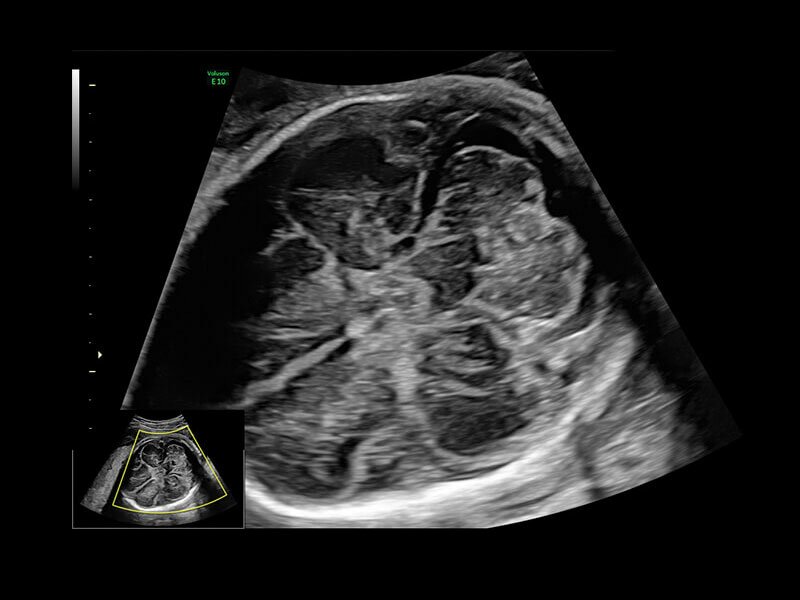

Клинические изображения

• Программа 3D и режим инверсии (при наличии специализированных датчиков)

• Томографический ультразвук (TUI)

• Объемное контрастирование прямой плоскости - Basic VCI (VCI-A + VCI static)

• Advanced VCI (Volume Contrast Imaging) - расширенный программный пакет объемного контрастного изображения (VCI) для механических и электронных объемных датчиков:

• Проведение любой произвольной плоскости в 3D/4D (OmniView)

• Объемное контрастирование любой произвольной плоскости (OmniView+VCI)

• Регулировка толщины и формы коронарного среза в 3D/4D (получение коронарной плоскости в 3D/4D, например, для оценки мозолистого тела - автоматическая функция "Corpus Callosum"

Объемное сканирование Voluson — 3D/4D вашей мечты

Объемное УЗИ на Voluson E10 — это не просто потрясающе красивая картинка, это ценный инструмент получения дополнительной информации при обследовании женщин.

Voluson E10 поддерживает инновационные технологии формирования изображений — HDlive Silhouette и HDlive Flow, которые позволяют увидеть мельчайшие детали. Алгоритм SonoRenderlive упрощает рабочий процесс и дает возможность реконструировать изображение поверхностей, определяя область перехода между тканью и жидкостью.

• Усовершенствованный режим объемной визуализации с контрастированием (Volume Contrast Imaging, VCI) и опция OmniView

• Повышает контрастное разрешение и улучшает визуализацию области интереса в любой плоскости сечения, даже при исследовании структур неправильной формы.